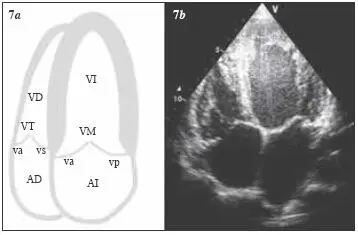

Para obtener este plano se debe dirigir el haz de ultrasonidos superior y medialmente hacia la escápula derecha, con la muesca del transductor apuntando hacia el flanco izquierdo del paciente, de tal forma que se obtenga un corte coronal del corazón que pase por el ápex cardiaco. Desde esta posición se visualizan las cuatro cavidades, los septos interventricular e interauricular, así como la crux cordis . Este plano es óptimo cuando se consigue obtener los ejes largos máximos de ambos ventrículos, así como la máxima excursión de las válvulas mitral y tricúspide (valvas anterior y septal). El ápex aparecerá en la parte superior de la pantalla y las aurículas en la parte inferior de ésta; las cavidades derechas, en la parte izquierda, y las izquierdas, en la derecha. La valva septal de la tricúspide se inserta en una región más apical del septo membranoso que la valva anterior mitral (de 5 a 10 mm en niños mayores y en adultos), lo que nos permitirá diferenciar las válvulas auriculoventriculares y las cavidades ventriculares acompañantes ( fig. 3.7).

Fig. 3.7 Plano apical de cuatro cámaras. AD = aurícula derecha; AI = aurícula izquierda; VD = ventrículo derecho; VI = ventrículo izquierdo; VM = válvula mitral (va, valva anterior; vp, valva posterior); VT = válvula tricúspide (va, valva anterior; vs, valva septal).

Éste es uno de los principales planos ecocardiográficos, ya que al poder ser visualizadas las cuatro cavidades del corazón, se pueden evaluar sus tamaños relativos, su orientación y su integridad estructural. Dado que se pueden valorar de manera simultánea los septos interauricular e interventricular, este plano va a tener una especial relevancia en cardiología pediátrica.